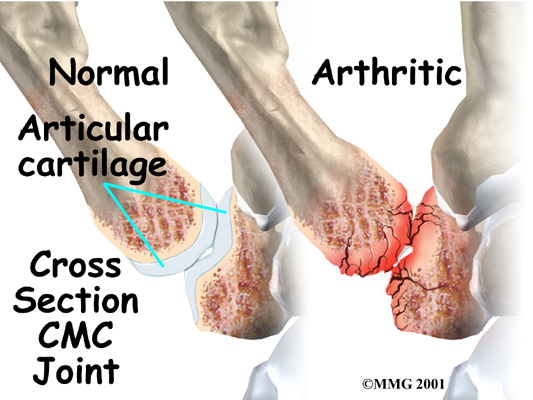

The joint surfaces are covered with a material called articular cartilage. This material is the slick, spongy covering that allows one side of a joint to slide against the other joint surface easily. When this material wears out, the joint develops a type of arthritis called osteoarthritis and becomes painful. Osteoarthritis is the most common form of arthritis occurring at this joint.

Arthritic joint surfaces can be a source of stiffness, pain, and swelling. The artificial joint is used to replace the damaged joint surfaces so patients can do their activities with less pain. Unlike a fusion surgery that simply binds the joint together, arthroplasty can help take away pain while allowing the thumb joint to retain movement.